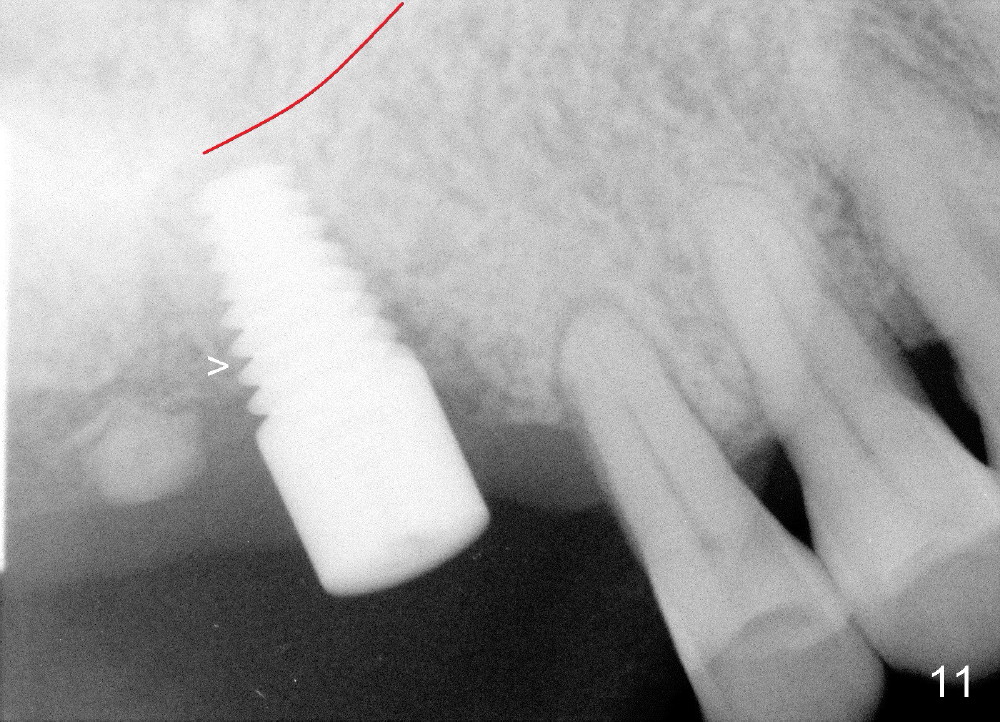

There is no nasal hemorrhage intra or postop. The implant is covered buccally by healing gingiva 7 days postop (Fig.9). It appears that the gingiva has strong regenerative potential. The buccal gingiva looks normal 3 months postop (Fig.10 healing cuff is placed over the implant). The implant appears to have osteointegrated (Fig.11).